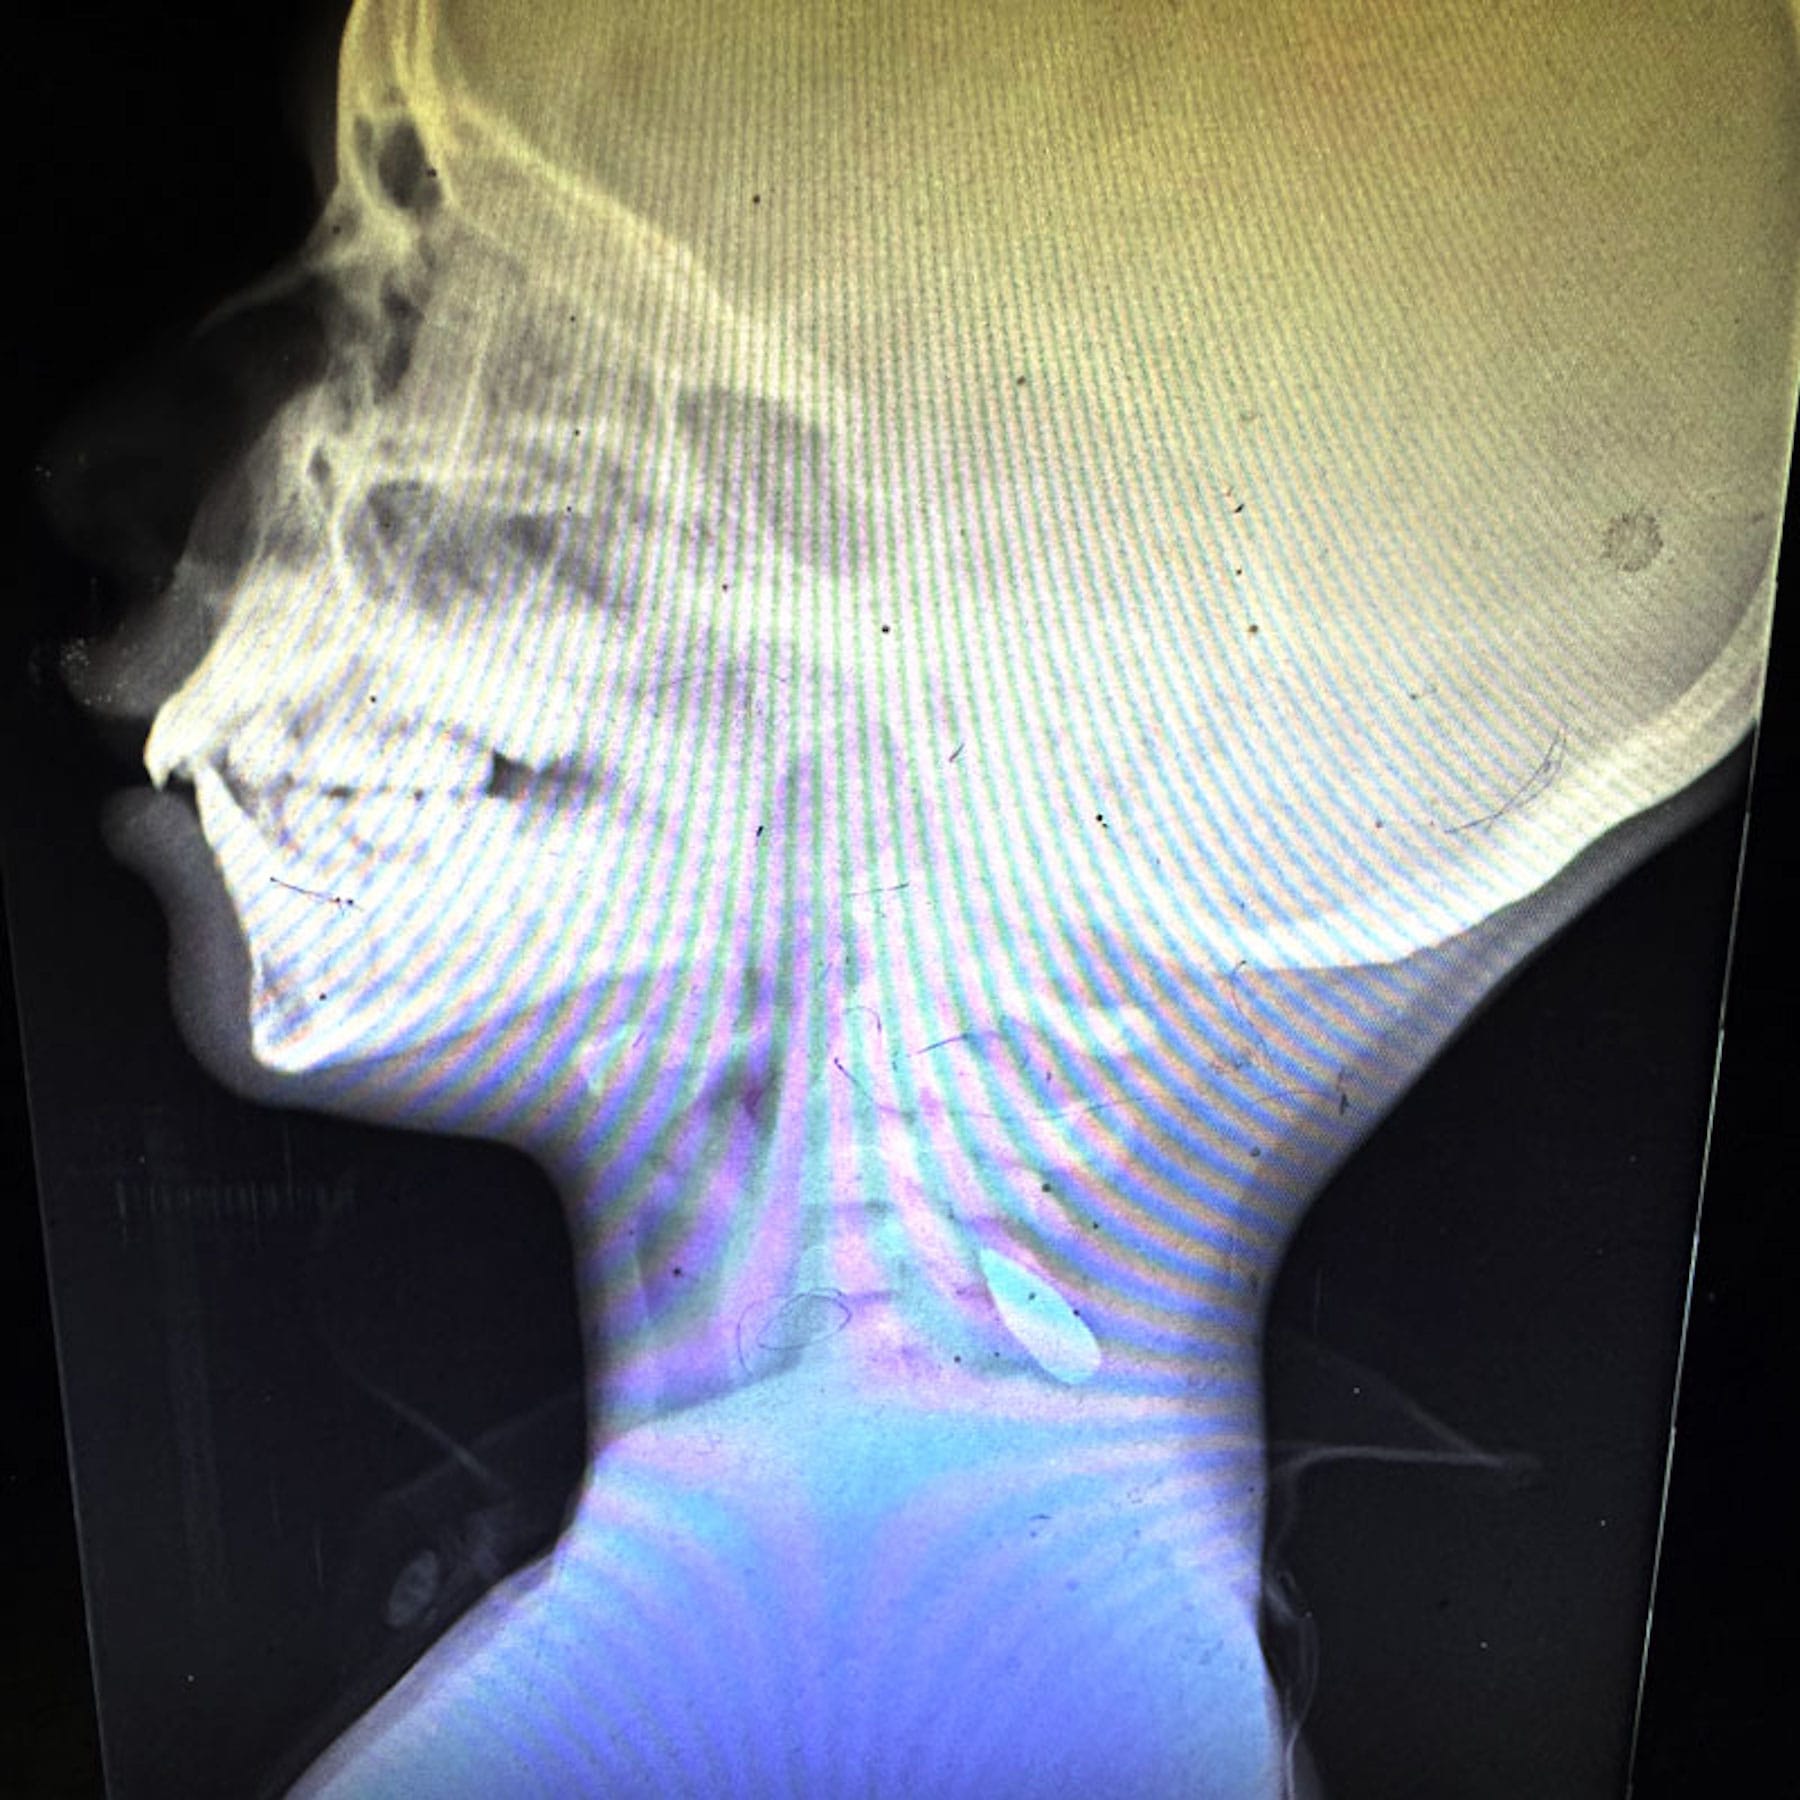

“One night in the emergency department, over the course of four hours, I saw six children between the ages of 5 and 12, all with single gunshot wounds to the skull,” Dr Mohamad Rassoul Abu-Nuwar, a surgeon from Pittsburgh, said.

23-year-old paramedic Rania Afaneh said shetreated a child who had been shot in the jaw. The child was fully conscious but couldn’t stop choking on his own blood, she said.